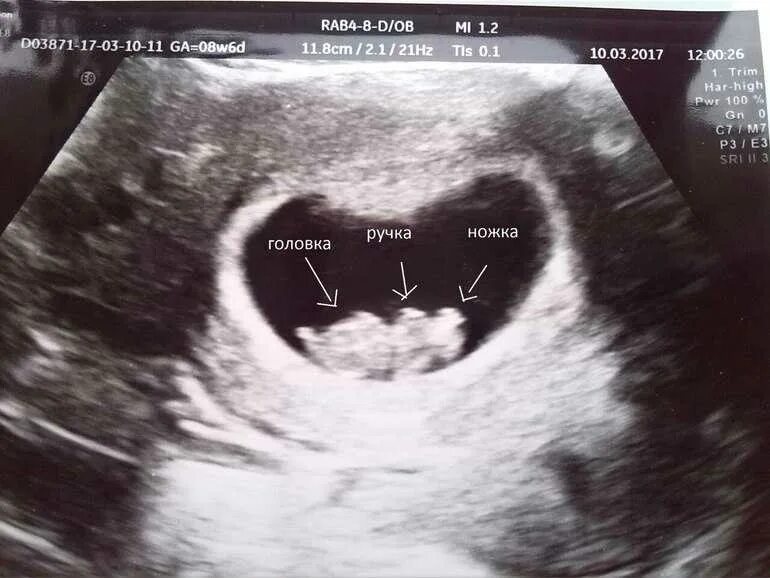

Почему замирает беременность на 6 7